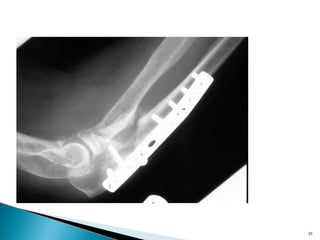

•Resist axial load by applying force at 90 degree to the axis of

potential deformity

•Metaphyseal tibial plateau split fractures

• Used when the fracture will only displace in one direction

• Only useful in metaphyseal fractures

• Applied so as to resist one deforming force

•Resist axial loadby applying force at 90 degree to the axis of potential deformity •Metaphyseal tibial plateau split fractures 24

• Used whenthe fracture will only displace in one direction • Only useful in metaphyseal fractures • Applied so as to resist one deforming force 25